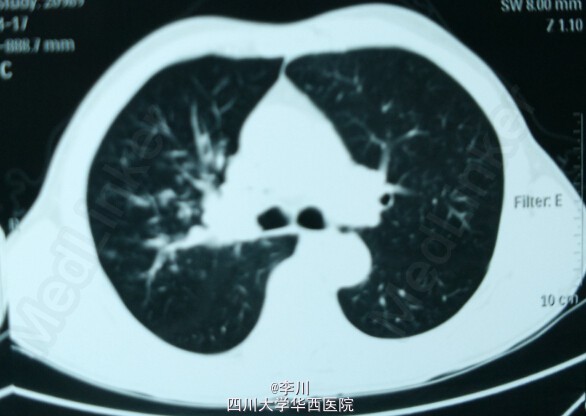

患者,男,63岁,因“咯血10天,发现右肺上叶鳞癌5天”入院。10天前患者无明显诱因出现咳嗽,咯血,为鲜红色,量约100ml,于当地医院行CT检查提示:右肺上叶支气管内充盈缺损,增强扫描不均匀强化。

在全麻下行VATS右肺上叶切除术+支气管袖式成形术+淋巴结清扫术,术中见肿块位于右肺上叶支气管开口,约1.5cm*1.5cm*1.2cm大小,无脏层胸膜皱缩、无侵犯壁层胸膜;肿瘤距隆突 <2cm,2、3、4、7、9、11、12、13组淋巴结肿大。术后患者送人胸外ICU,予以呼吸机辅助呼吸、心电监护、抗感染、祛痰等对症支持治疗。